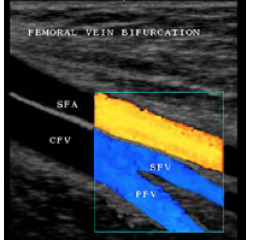

what variant is diplayes in this image?

what venous variant can be partial or complete and has a prevalance of ~ 20%

duplicated SFV (also below). notice proximal 1 SFV then divides into 2 SFV’s and distally rejoins into 1 SFV.

Why can’t it (image below) be a CFV bifurcating into SFV and profunda?there are 2 superiorly and 2 inferiorly

duplicated (bifid) SFV and popliteal veins